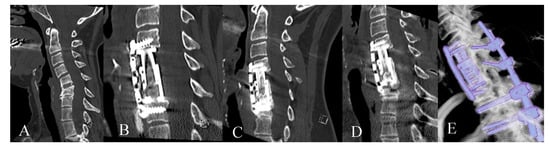

2. Materials and Methods

3.2. Radiological Outcome